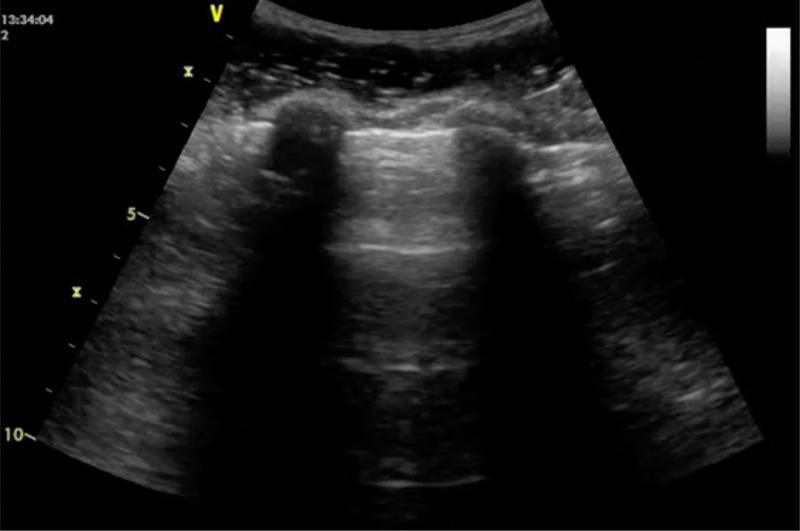

• Lignes A : artefacts horizontaux parallèles, équidistants, répétés sous la plèvre.

Les lignes A sont des réverbérations horizontales répétées, parallèles à la plèvre.

Elles s’estompent progressivement avec la profondeur.

Origine – Ces artefacts sont dus à la réflexion répétée des ultrasons entre la plèvre et la sonde, à l’interface air–tissu.

Interprétation – La présence de lignes A indique un poumon bien aéré, sans surcharge interstitielle ni condensation.

A comme Air : un profil A pulmonaire traduit une ventilation normale.

Lignes A + glissement pleural. © POCUS Atlas